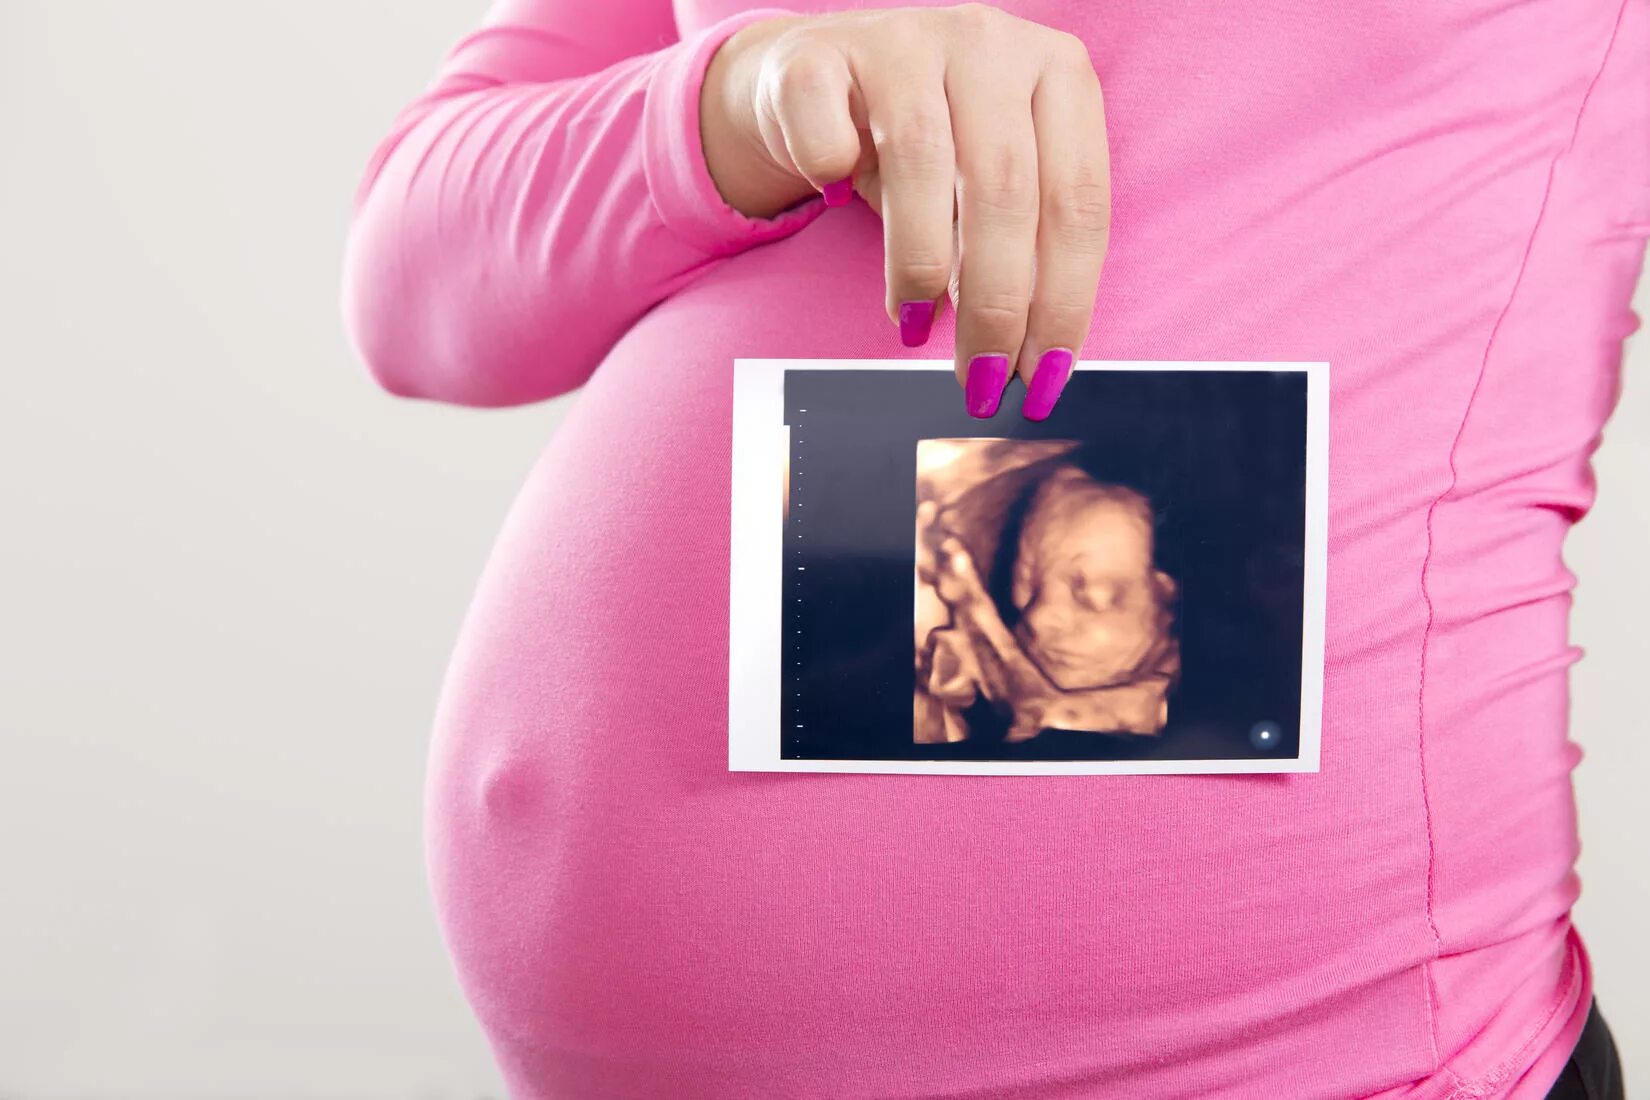

На каком сроке делать 3д